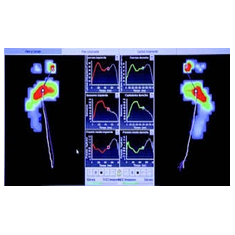

Biomecánica

Estudios de la marcha video 2d

podologo bogota Equipos Médicos para Diagnóstico podologo bogota

podologo bogota Equipos Biomédicos de Alta Tecnología podologo bogota